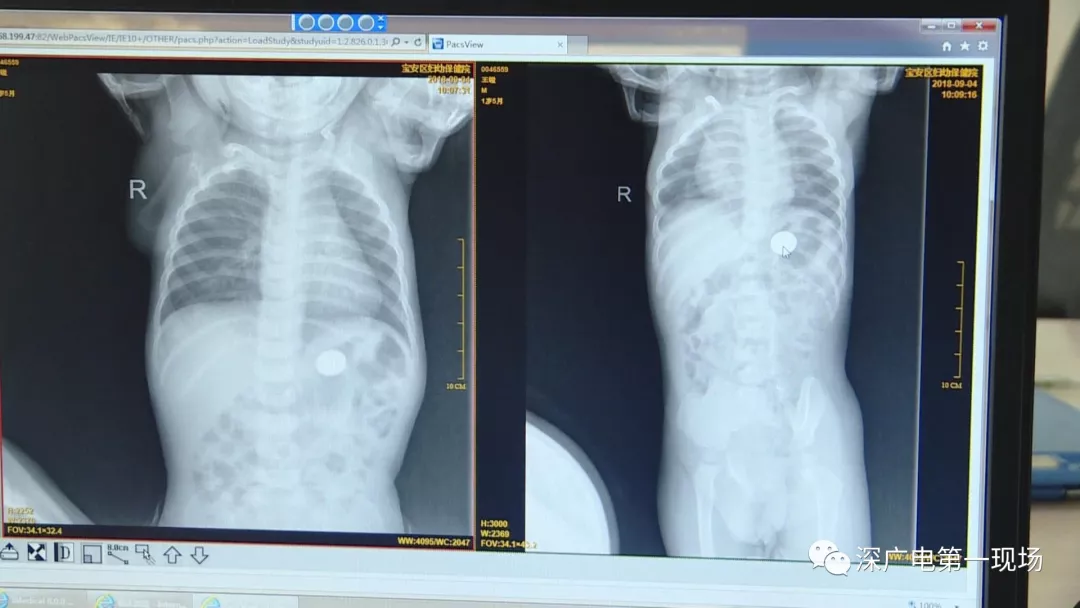

在術(shù)前檢查中

細(xì)心的醫(yī)生竟從

孩子的胸片中有了意外發(fā)現(xiàn)

9月4號(hào),一名1歲零5個(gè)月的男嬰因在家中摔傷,被父母送到了寶安區(qū)婦幼保健院,醫(yī)生診斷為左側(cè)尺橈骨骨折。在進(jìn)行全麻手術(shù)之前,院方例行對(duì)嬰兒進(jìn)行了周身檢查。手術(shù)前,兒外科醫(yī)生趙冠聰在查看患者的胸片時(shí),發(fā)現(xiàn)這名嬰兒的胃部有一枚硬幣大小的暗影。

在與多名醫(yī)生會(huì)診之后,醫(yī)生擬定了聯(lián)合手術(shù)方案。

胃部取出一角硬幣

已吞咽半月之久

經(jīng)過(guò)兩個(gè)小時(shí)的時(shí)間,兒科醫(yī)生郭景濤為患兒取出了藏在胃底的一角錢(qián)硬幣。目前,患兒已經(jīng)痊愈出院。